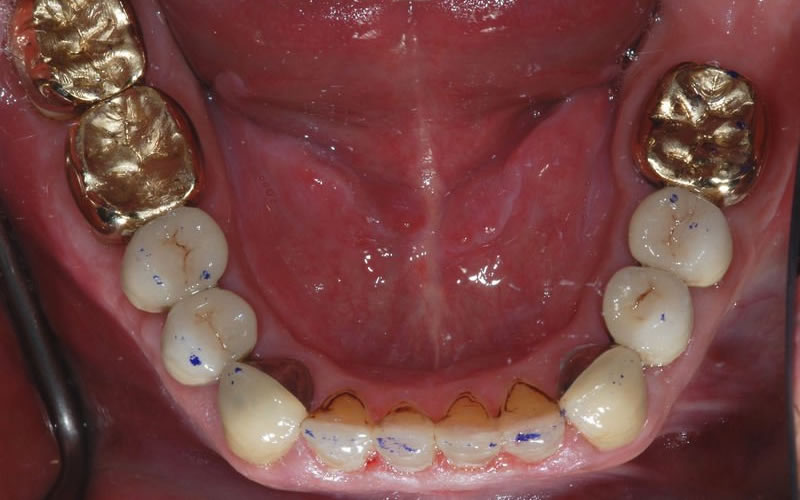

Case Studies

Dental Crowns (7 images)

Upper crowns and lower composites (4 images)